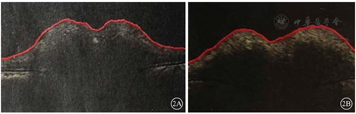

患者女,26岁。因四肢乏力伴双眼视物模糊3月余,加重2周于2021年2月8日就诊于河北大学附属医院神经外科。询问病史,2020年11月中旬,患者无明显诱因出现复视伴四肢乏力、腰部束带感,以右侧为重,未予重视;2020年12月中旬,患者因四肢乏力行走时摔倒出现右眼轻微视物模糊,但复视症状消失,于当地医院行头颅磁共振成像(MRI)检查未见明显异常,未予特殊治疗;其后右眼视力逐渐下降至眼前数指,四肢乏力进一步加重。就诊于河北大学附属医院神经外科门诊行头颅及脊椎MRI检查,提示脑积水、间质性脑水肿可能(图1A);C2~C7椎体水平硬膜下脊髓外异常信号(图1B,图1C,图1D)。神经外科以"颈椎管硬膜下髓外占位"将患者收入院。等待手术过程中,患者左眼视力急性下降至眼前数指,请眼科会诊。眼部检查:右眼视力手动/5 cm,左眼视力数指/5 cm。眼底检查,双眼视盘水肿。腰椎穿刺检查,颅内压正常,考虑与脑积水相关。眼科会诊诊断:双眼视盘水肿。建议治疗原发病。2021年2月21日,患者于全身麻醉下行椎管内占位切除(C2~C7水平段)联合椎管成形手术。手术后病理检查结果提示椎管占位-神经鞘瘤,部分区域细胞增生活跃。手术后患者肢体症状基本恢复,于2021年3月7日出院。出院时右眼视力光感,左眼视力数指/1 m。手术后25 d复查,患者双眼视力无明显改善;光相干断层扫描(OCT)检查,双眼视盘仍有水肿(图2)。